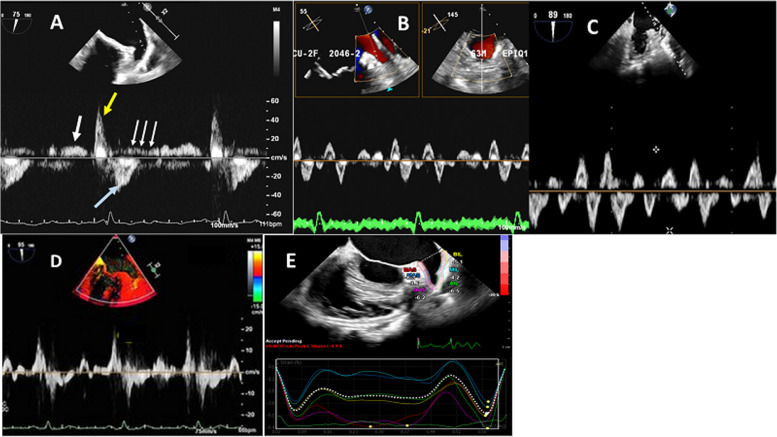

心肌栓塞性中风是心房颤动(房颤)最严重、最危及生命的并发症,12 个月的相关死亡率高达 30%。瓣膜性房颤中约 47% 的血栓和非瓣膜性房颤中 91% 的血栓位于左心房附壁(LAA)。因此,在许多临床情况下,识别或排除 LAA 血栓至关重要。在房颤消融术和 LAA 封堵术等介入手术之前、期间和之后,使用成像模式(尤其是超声心动图)评估 LAA 形态和功能至关重要。这篇综述文章介绍了 LAA 的解剖、生理和病理背景,随后对不同的超声心动图模式进行了评估。其中包括许多实用要点,以提高诊断准确性并尽量减少图像采集和解读过程中的误差。在每个以 LAA 为关键目标的临床场景中,都收集了具体而重要的信息和参数。

Cardioembolic stroke is the most serious and life-threatening complication of atrial fibrillation (AF), with an associated mortality up to 30% at 12 months. Approximately 47% of thrombi in valvular AF and 91% of thrombi in nonvalvular AF are localized in the left atrial appendage (LAA). Therefore, identification or exclusion of LAA thrombi is critical in many clinical situations. It is essential to assess LAA morphology and function using imaging modalities (particularly echocardiography) before, during, and after interventional procedures such as AF ablation and LAA occlusion. This review article describes the anatomical, physiological, and pathological background of the LAA, followed by an assessment of different echocardiographic modalities. Many practical points are included to improve the diagnostic accuracy and to minimize errors during image acquisition and interpretation. In each clinical scenario where LAA is the crucial target, specific and essential information and parameters are collected.